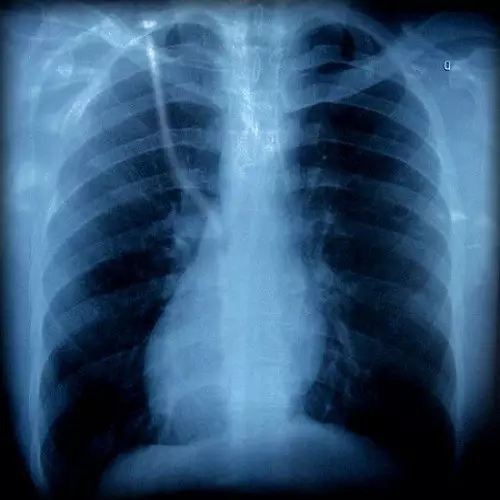

胸片有異

胸外科

咳嗽可以是由肺部腫瘤等疾病引起的,如果胸片或胸部CT上發(fā)現(xiàn)有可疑病變時,應該看看胸外科。一般,呼吸內(nèi)科大夫也會幫忙轉(zhuǎn)診的。